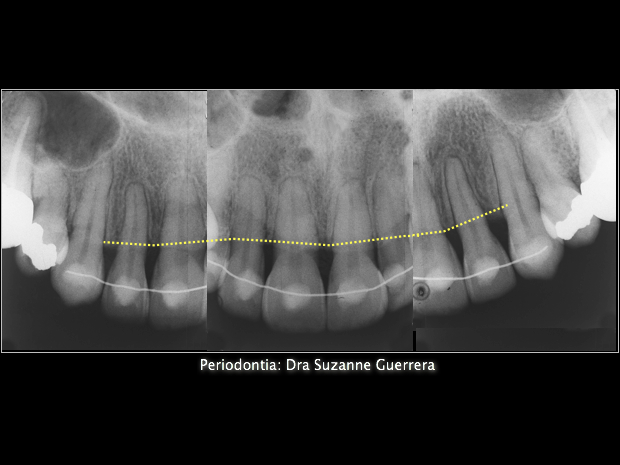

Imagem radiográfica da perda óssea pré-existente na região dos incisivos superiores

1. Imagem  radiográfica final evidenciando a  manutenção dos níveis ósseos